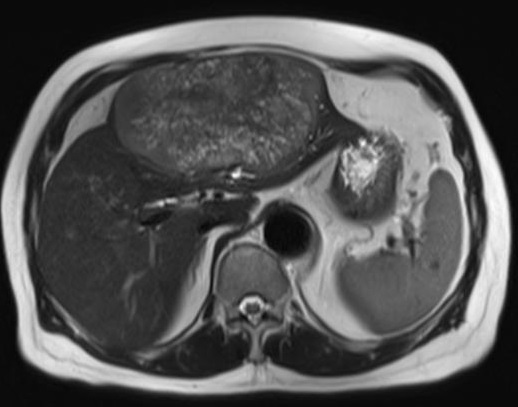

Image IRM du

carcinome hepatocellulaire : Image du masse a

iso ou hyposignal en T1 et hypersignal en T2 . Rehaussement

au temps arteriel et " wash out " au temps portal .

Image IRM enT1 du

carcinome hepatocellulaire : Aspect lesionaire

est isointense du foie droit ( fleche rouge ) . Foie

est en cirrhose , ascitique |

Image d'une carcinome

hepatocellule du foie droit en aspect une masse

nodulaire , hypersignale . Foie est en

cirrhose et ascite . Image IRM en T2 |